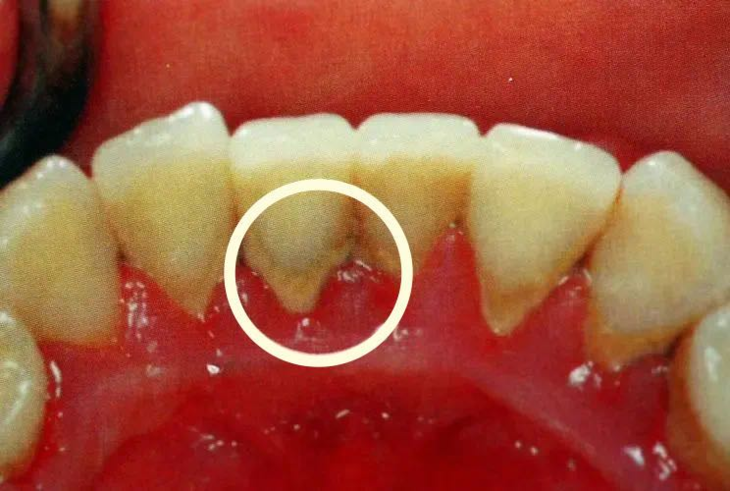

牙菌斑越积越多,硬化形成牙结石,寄居在牙结石上的细菌会产生酸性物质,开始逐步破坏我们的牙齿,刺激牙龈,造成牙龈肿痛出血,这便是牙周炎的早期症状。

但是,很多人没有意识到这是牙周炎症,只是把这种症状当成简单的“上火”来处理,于是喝凉茶、吃降火药等熟悉的操作就会跟上。这些办法不但难以解决牙齿根本问题,反而掩盖了问题的真相。久而久之,牙结石越堆积越多,牙周炎症越来越严重,牙龈肿痛加重,一些人一般会用消炎药加以应对。结果牙龈逐渐萎缩,牙槽骨也随之吸收萎缩,牙根失去充足的支撑,牙齿开始松动、摇晃。